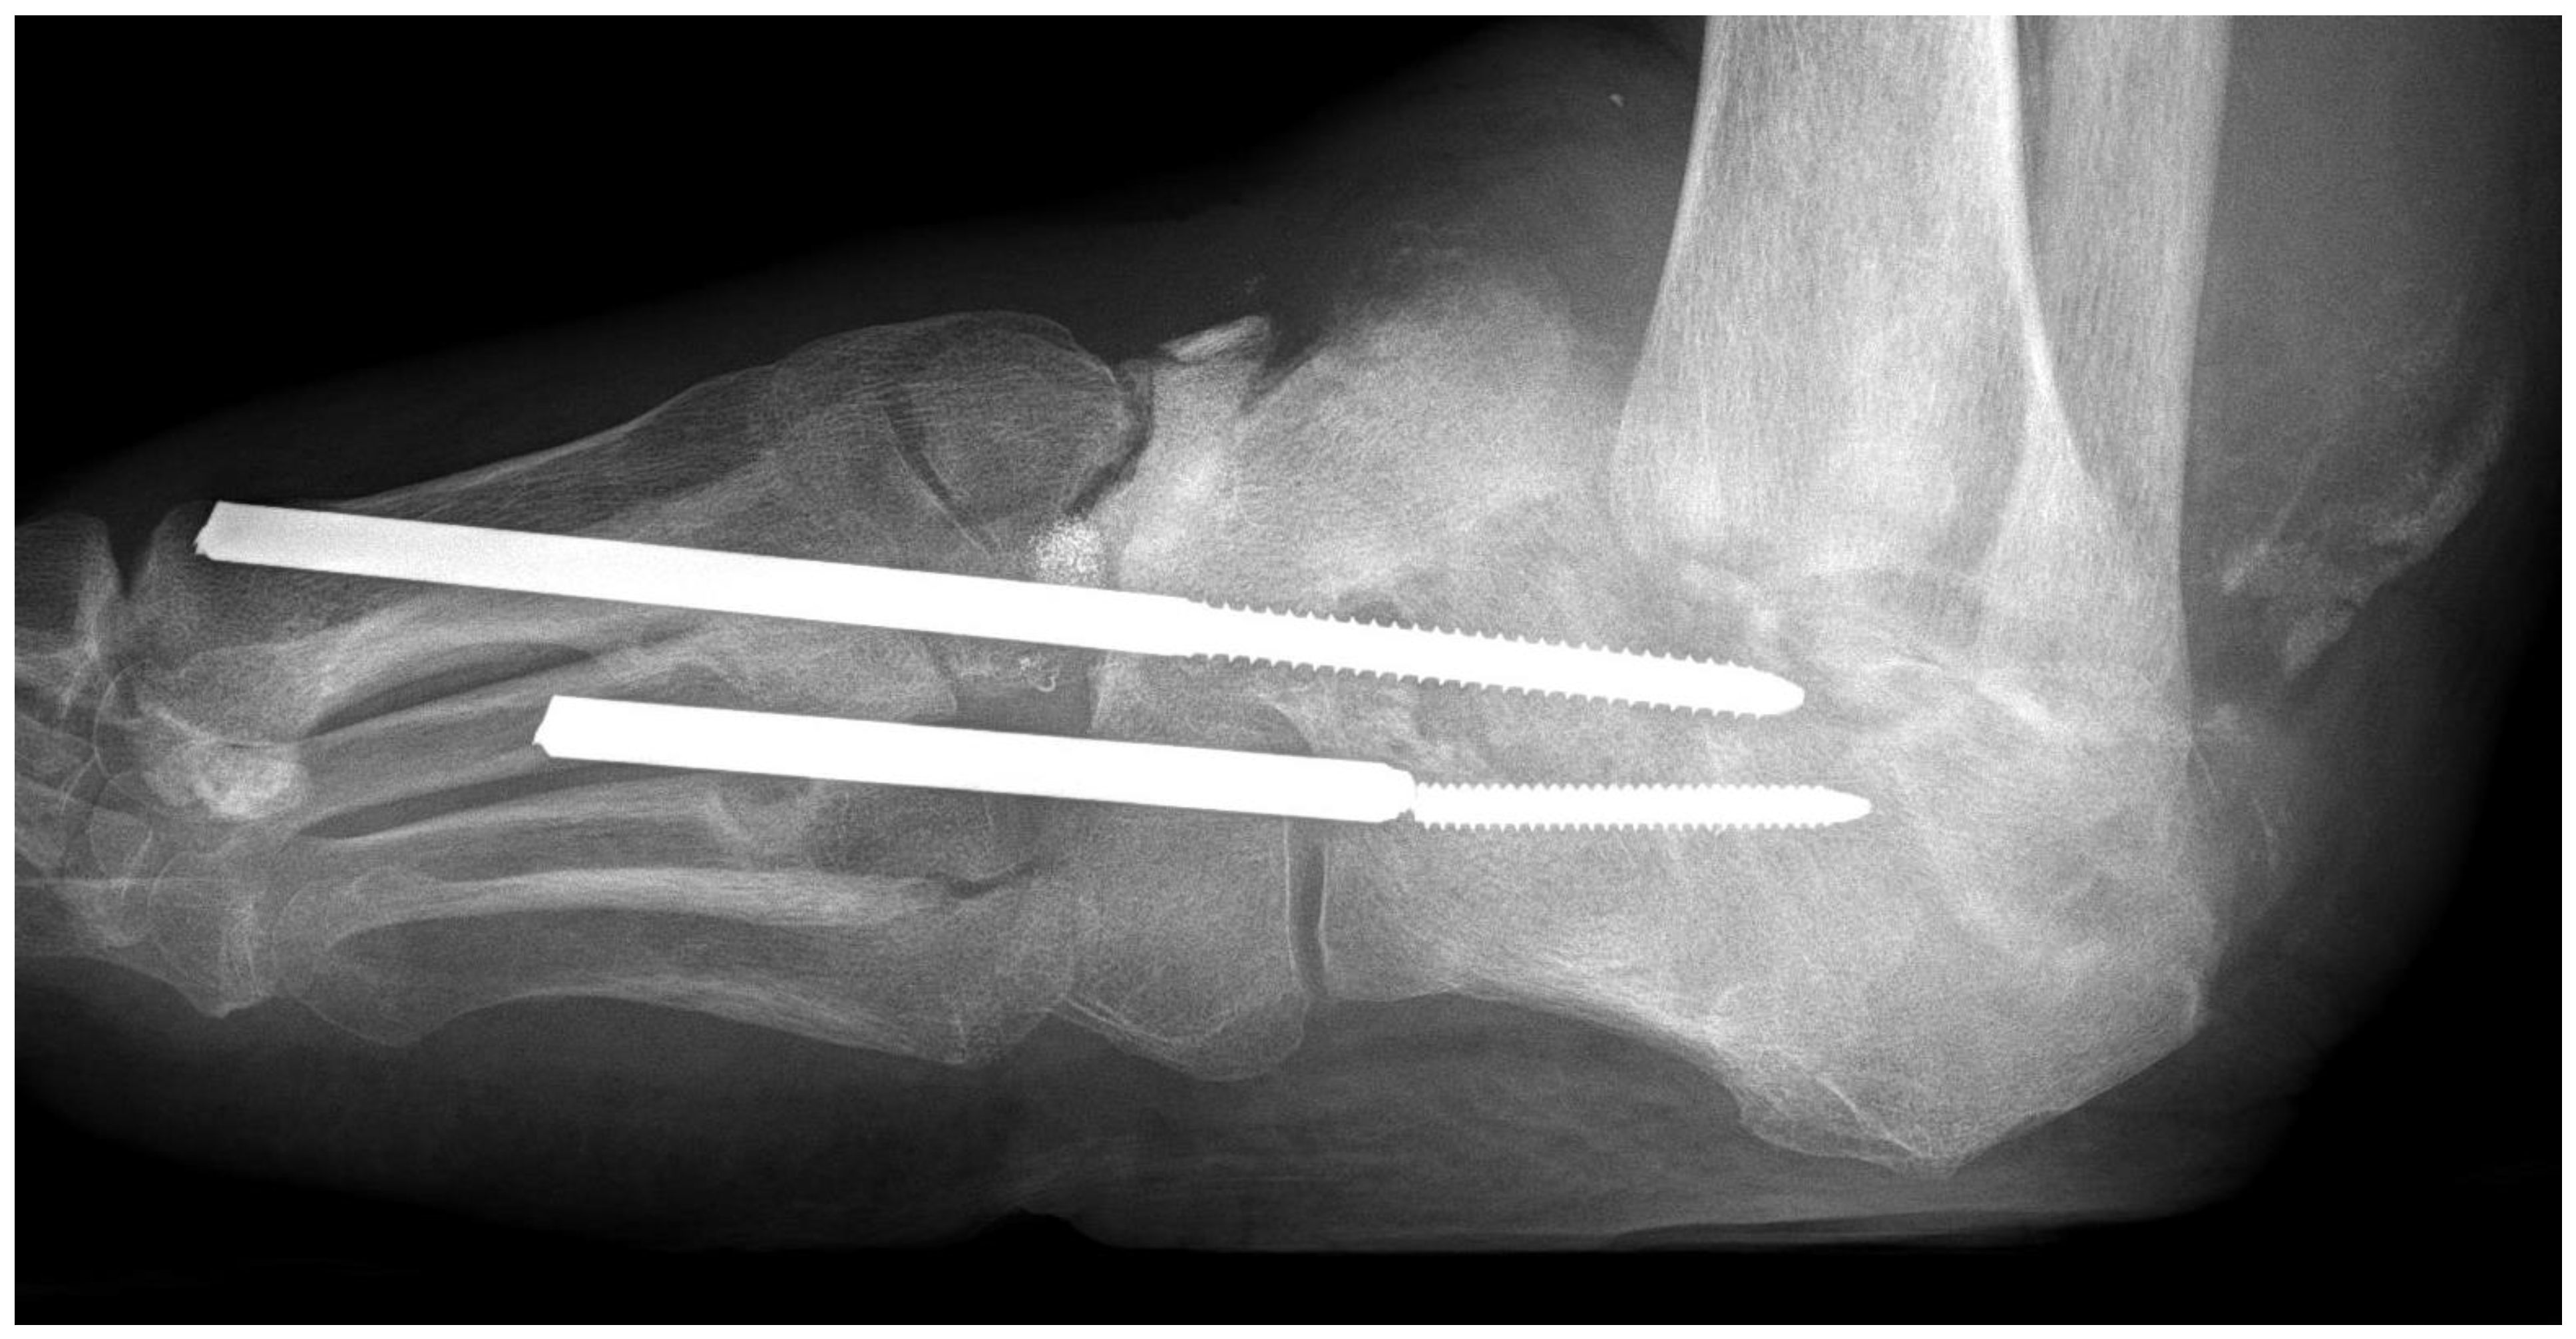

4.1. Skeletal Problems

| skeletal changes | rare | frequent (Charcot foot) |